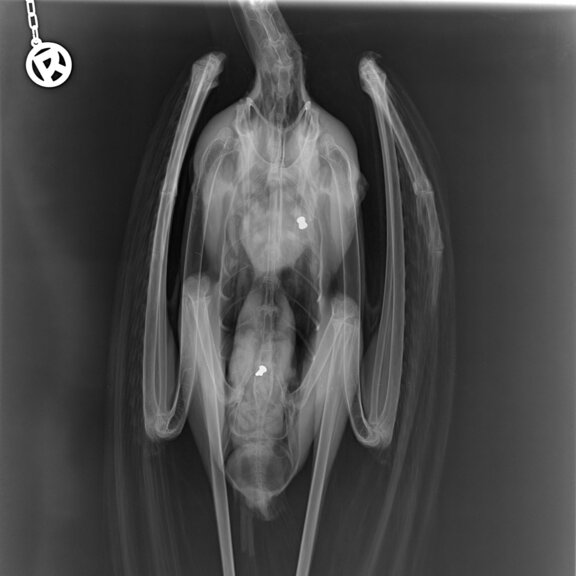

Angeschossener Graureiher.

Im August ist ein verletzter Graureiher durch eine aufmerksame Finderin in die Wildtierstation Sachsenhagen gebracht worden. Bei der Eingangsuntersuchung wurde eine Schussverletzung festgestellt. Die vom Stationsleiter und Fachtierarzt für Wildtiere Dr. Florian Brandes vorgenommene röntgenologische Untersuchung ergab als Befund, dass zwei Luftgewehrprojektile im Vogel stecken. „Es ist unglaublich, dass Personen einfach auf geschützte Wildvögel schießen. Das arme Tier ist durch die Schussverletzungen flugunfähig“, ärgert sich Dr. Brandes. Die Wildtierstation hat den Fall bei der Polizei Wunstorf zur Anzeige gebracht, der Graureiher ist in Großenheidorn (Region Hannover) gefunden worden. Der Graureiher ist am nächsten Tag operiert worden, eine Kugel konnte entfernt werden, die andere wurde an Ort und Stelle belassen, weil sie so tief in der Muskulatur steckte, dass sie nicht hätte entfernt werden können ohne größere Schäden am Gewebe anzurichten. Der Reiher befindet sich auf dem Weg der Besserung, „Wir hoffen, ihn bald wieder auswildern zu können“ so Dr. Brandes. Zurzeit befindet sich der Vogel in der Außenanlage der Wildtierstation.

Röntgenbild des Graureihers mit Luftgewehr Projektilen.